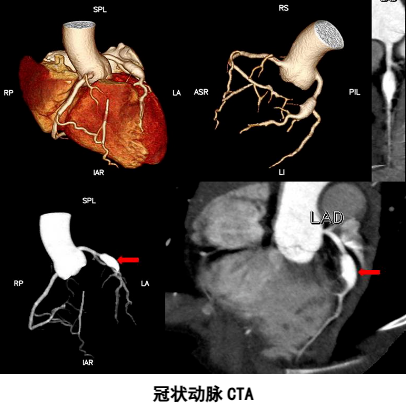

冠状动脉CTA检查:

(1)疑有冠状动脉狭窄及血流动力学异常者;

(2)怀疑冠心病,运动试验结果不确定者;

(3)可疑冠状动脉发育异常者;

(4)长期不明原因胸闷、胸痛,其它检查无异常发现者。